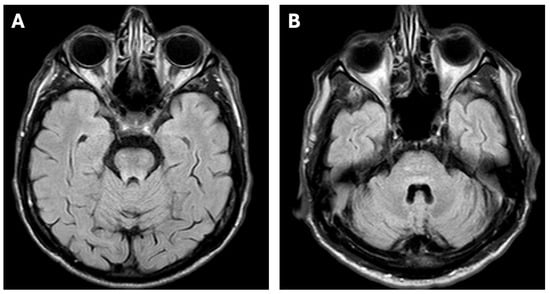

2. Case Report